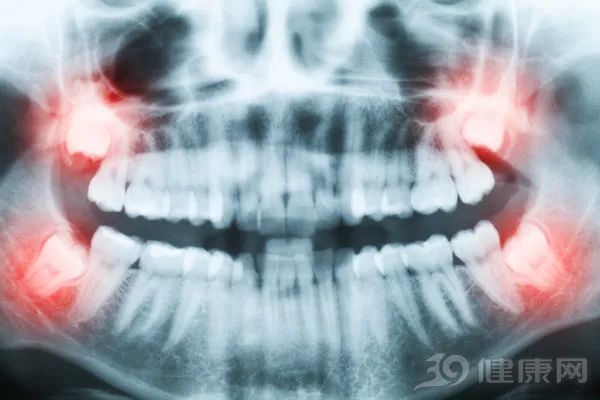

1、智齿

去医院看牙科,如果长出了智齿,医生一般会建议拔掉,难道智齿不是正常的牙齿吗?在人类进化的过程中,智齿确实起过不少的作用。

反而有时候,智齿不能完全萌生出来或者只能萌生一半,会影响牙齿健康。